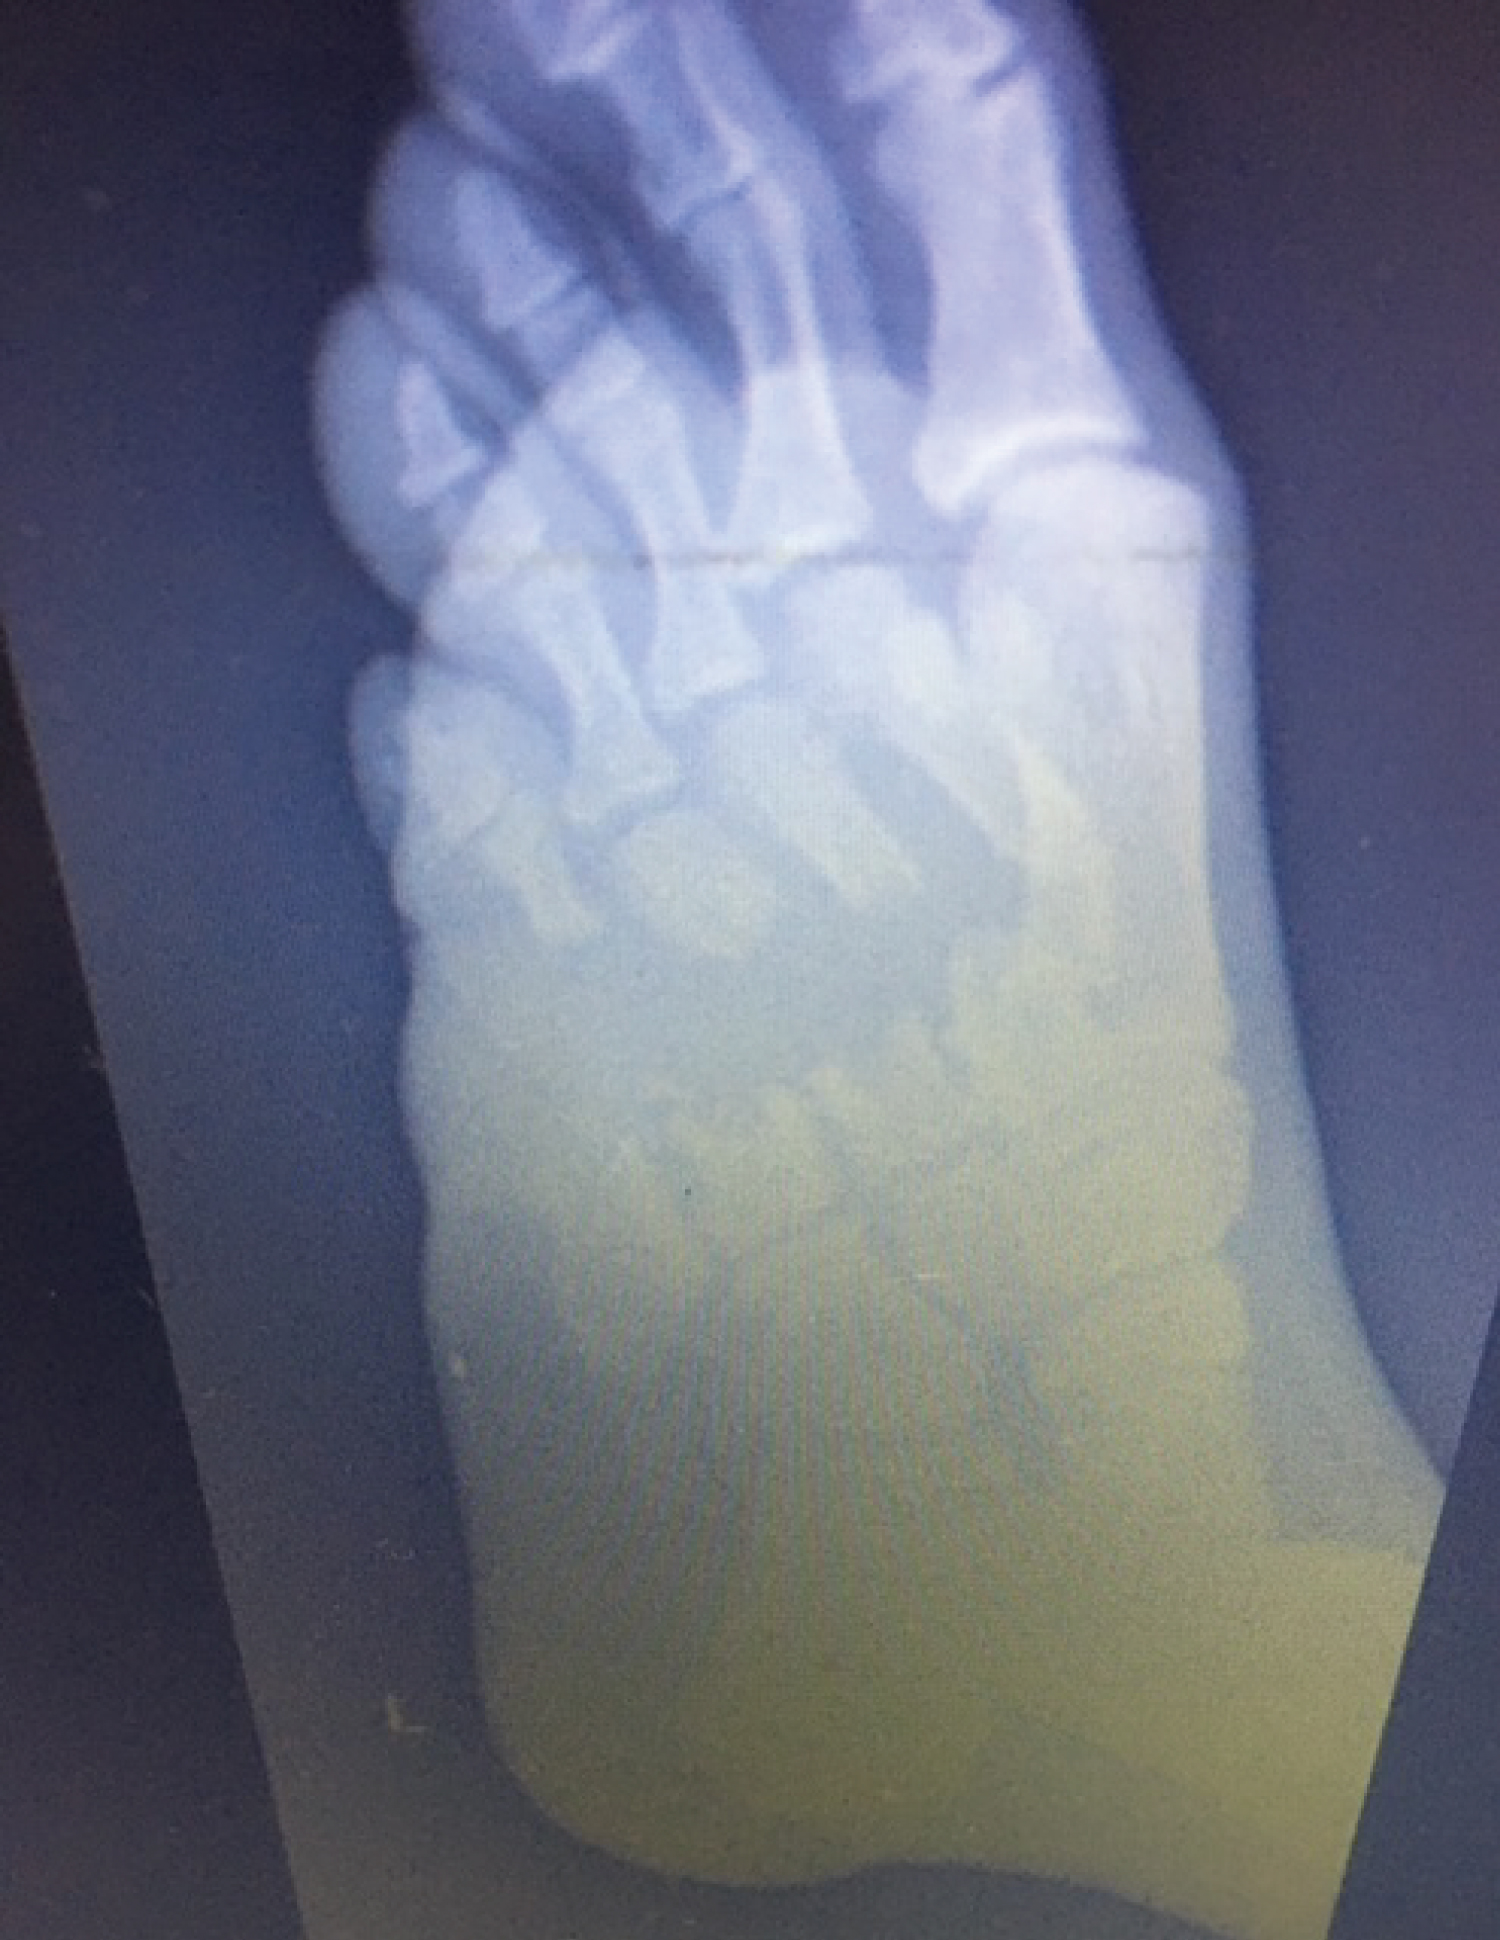

A 25-year-old soldier was involved in a blast and suffered multiple superficial and deep soft tissue injuries. His main osseous injuries were in his left foot, where he suffered fractures of his second, third, fourth and fifth metatarsals. These metatarsal injuries were open fractures with segmental bone loss and soft tissue loss with significant contamination (Figure 1 and Figure 2). He also had a large soft tissue defect from damage to his calf complex with no involvement of the neurovascular structures on the unilateral side (Figure 3). He was initially managed as per ATLS principles ensuring physiological stability. He then went on to have acute debridement of the multiple soft tissue injuries planned in conjunction with the plastic surgery team.

Figure 1: Soft tissue loss with contamination. View Figure 1

Figure 2: Radiograph shows segmental bone loss. View Figure 2